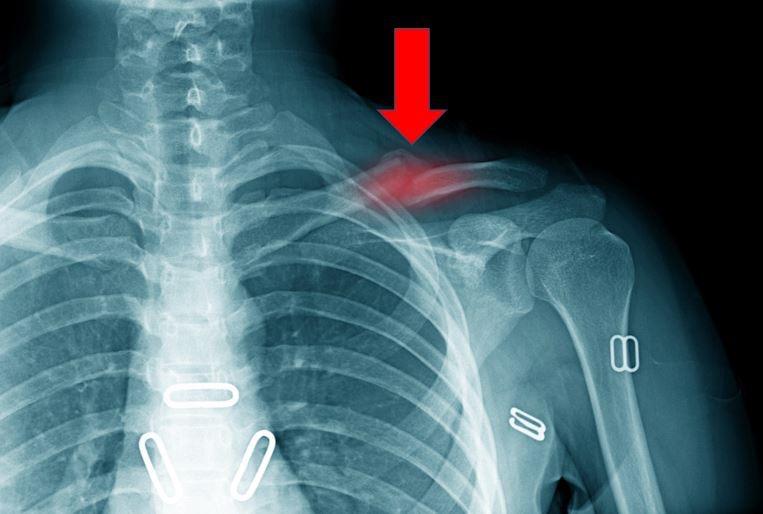

The clavicle is one of the most accidentally fractured bones in the human body, mostly as a result of falls on an outstretched arm or on the shoulder. The medical evidence supports the fact that the clavicle is one of the easiest bones in the body to break. (1) The clavicle is one of the only bones that given the opportunity I would attempt to break. If I struck the clavicle and it did not break, I would simply move on to another technique. I have direct experience with one fracture of the clavicle related to a martial an elbow strike. I have witnessed and treated many clavicle fractures due to throws and falls and these occurred mainly among practitioners of Judo, Jujitsu, and Aikido. Frankly, you are more likely to cause a clavicle fracture with a throw than with a strike.

Photograph 6. Fracture of the clavicle.

The clavicle is easily accessed due to its position and location on the anterior superior shoulder area. When the clavicle breaks it usually breaks in one location, although multiple fractures of the clavicle are not uncommon. The clavicle is S shaped and the most common site of fracture is on the body of the clavicle in the direction of and closer to the shoulder. If you feel your own clavicle it will be the location away from the sternum at which point the clavicle is generally thicker and has a very strong arch shape and if you feel along the clavicle towards the shoulder you will find an area along the body of the clavicle that is thinner. This is the easiest breaking point of the clavicle and where most blunt force trauma clavicle fractures will occur. Like everything there are exceptions to the rule due to personal differences in anatomical structure, bone thickness and density.